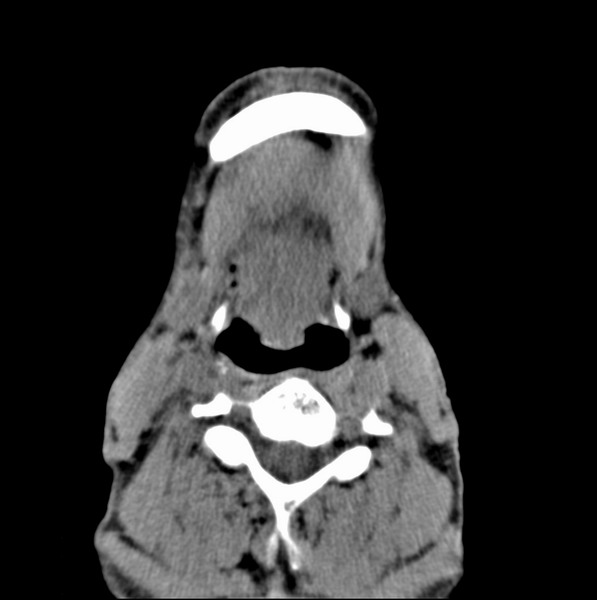

男、60、舌根肿物。

舌垂直肌和横肌影处肿块影,边缘不规则,咽腭扁桃体及舌下间隙脂肪影消失,病变侵及口咽。

考虑-----舌根癌

舌跟软组织肿块,较大有坏死,钙化。结合年龄一般是恶性肿瘤。

舌根部较大软组织肿块,其内见坏死低密度区及钙化影;考虑舌根癌可能。